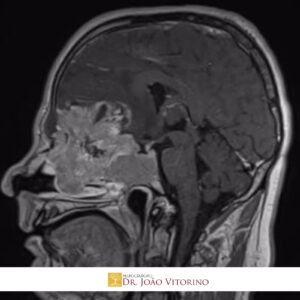

Meduloblastoma: Diagnóstico, Tratamento e Perspectivas na Neurocirurgia

O meduloblastoma é o tumor maligno mais comum do sistema nervoso central em crianças, embora também possa ocorrer em adultos. Localizado geralmente na região do